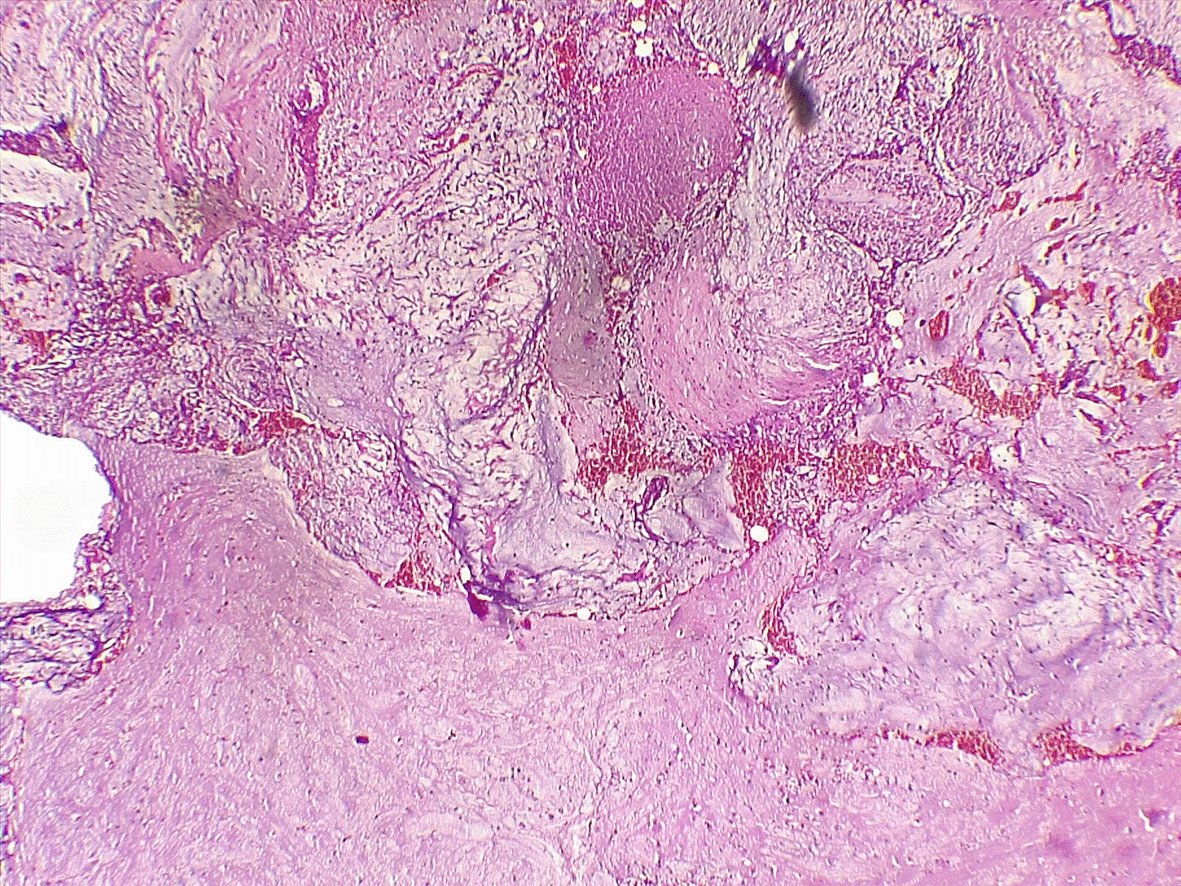

An 81-year-old woman with a history of diabetes mellitus, hypertension, arterial fibrillation, and ventral hernia repair was scheduled to undergo surgery for a recurrent hernia. She consulted an emergency department for rapidly increasing abdominal pain for 6 days. Upon examination, the umbilicus bulged with overlying sphacelous skin (Figure 1). Biology was as following: CRP = 167.3 mg/L, WBC = 12020/mm3, creatinine = 121.84 μmol/L, urea 9 mmol/L, hemoglobin = 12.3 g/dL. An abdominal CT scan revealed a herniated right colon through a 25 mm defect, an enlarged appendix measuring 18 mm, and communication with a 5 cm intrasaccular abscess (Figure 2). She then rushed to the operating theater. Upon incision, pus was evacuated from the hernial sac. The right colon was incarcerated within the aponeurotic defect, with no signs of digestive distress, and the peritoneal cavity was not contaminated due to the constriction ring at the neck of the sac. The appendix was gangrenous with a perforated tip eliciting mucus (Figure 3). Thorough lavage with appendicectomy and herniorrhaphy was performed. She died on 5th postoperative day to a pulmonary oedema. Histological analysis revealed a well-differentiated adenocarcinoma that developed within a serrated adenoma (Figure 4). It was classified pT3. Mucus was acellular (Figure 5). The hernial sac harbors similar cancerous cells.

Some cases have reported the presence of peritoneal carcinomatosis nodules in the hernial sac, mostly of the origin colon,9 and all were in the T3 or T4 stage.10 This could be explained by the drop metastases theory, where malignant cells metastasize following gravity, and inflammatory oncotaxis and chemotactic agents are probably operative mechanisms in the development of metastatic lesions in hernial sacs. Peritoneal metastasis consists of different phases. Cellular mechanisms involved in peritoneal spread can be ordered in sequential steps, such as detachment of malignant cells and increased motility, anoikis evasion, adherence to the peritoneal surface, invasion of the peritoneum, and colonization and survival in the new niche inflammatory oncotaxis and chemotactic factors are likely key mechanisms in the development of metastatic lesions within hernial sacs. The process of peritoneal metastasis involves multiple distinct phases. The cellular mechanisms underlying peritoneal dissemination can be described in a sequential manner, including: detachment of malignant cells accompanied by increased motility; evasion of anoikis; adherence to the peritoneal surface; invasion of the peritoneal tissue; and, finally, colonization and survival within the new microenvironment.11 However, extra-abdominal tumors (9.3% of metastatic tumors found during inguinal hernia repair, involving breast – thymus – pleura and hairy cell leukemia) have been reported to develop carcinosis nodules in the inguinal hernia sac.9 This could be explained by metastasis via the hematogenous route. In addition, mesothelioma of peritoneal origin can be identified as inguinal hernia.4 This statement suggests the promotion of routine examination of the hernia sac during surgery for a tumor with a co-existent hernia or any elective hernia repair, especially when gross pathology was not detected in the macroscopic examination of abdominal hernias in all cases,5 and that this situation is the initial presentation of malignancy in the third to half of cases.6,12,13 Further studies are needed to answer this question. Currently, selective microscopic examination is recommended in cases with grossly abnormal hernia sac specimens or macroscopically suspected lesions.14 Routine examination is not justified because of its high costs, with fees reaching €21,087.50, to detect a single case of malignant tumor in the hernia sac, as stated in a Spanish study.11